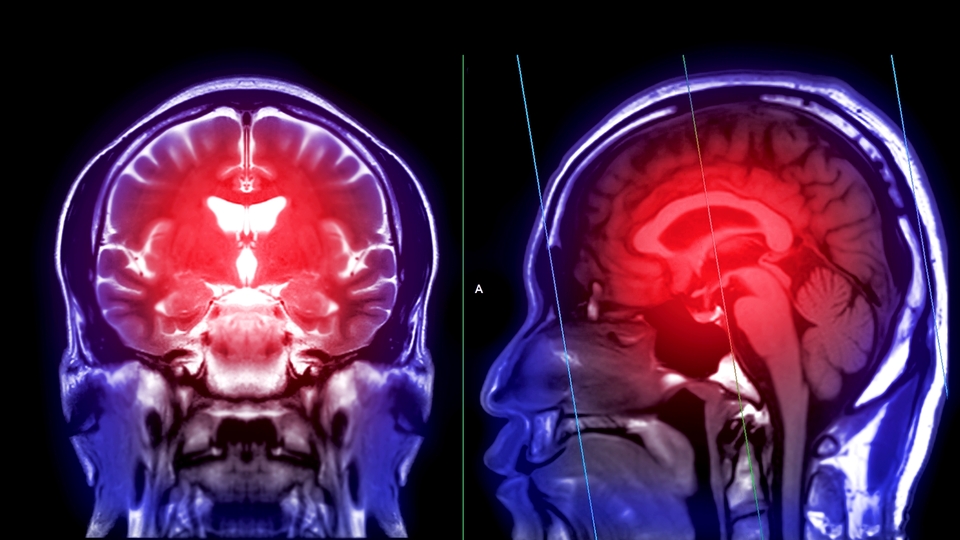

İnmenin her yıl dünya genelinde milyonlarca insanı etkileyen önemli sağlık sorunlarından biri olduğunu belirten Nöroloji Uzmanı Dr. Vugar Jafar, "'Acil bir beyin krizi' olarak tanımlanan inmede hastalığın seyrini belirleyen kritik unsur, erken müdahaledir. Beyne giden damarlardan birinin tıkanması sonucu gelişir ve tıkanıklık süresince her dakikada yaklaşık 1 milyon 900 bin nöron ölür. İnmede zamanla yarışmak, tedavi başarısının temelini oluşturur" dedi

Tedavide 'altın saat' olarak adlandırılan ilk 4,5 saatlik süreye dikkat çeken Uzm. Dr. Jafar, "Bu sürede özel kan sulandırıcı tedavilerle damardaki pıhtı çözülebilir. Uygun hastalarda girişimsel nöroloji uzmanları tarafından yapılan beyin anjiyografisi veya trombektomi işlemiyle pıhtı mekanik olarak çıkarılır ve ciddi oranda başarı sağlanır. Erken müdahale hastanın yaşam kalitesini korumaktadır. İnme sonrası rehabilitasyon süreci, fiziksel ve bilişsel iyileşmede büyük rol oynar. İnmede en güçlü tedavi, farkındalık ve zamandır" dedi.